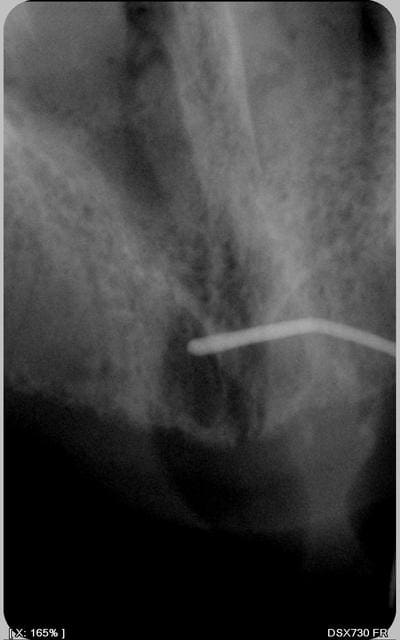

a quoi correspond cette radio : secteur médian ? cliché occlusal? rétroalvéolaire ?

j'ai l'impression d'y voir une lésion (granulome,kyste résiduel ou kyste naso-palatin)

radio retro au niveau de la suture inter palatine

... kyste du canal naso-palatin ... en forme de coeur?

Ne serait-ce pas tout simplement l'ostium du canal naso-palatin qui me semble t'il est un tout petit peu en arrière de la papille rétro incisive.

Mais normalement sa taille est plus modérée. alors???

La forme de cœur ou ovoïde est toujours visible dans les cas de kyste du canal naso- palatin. Le kyste palatale médian est aussi une version possible du kyste naso palatin

c'est pas un bout de racine enkylosé, qu'on voit sur ta radio du début?